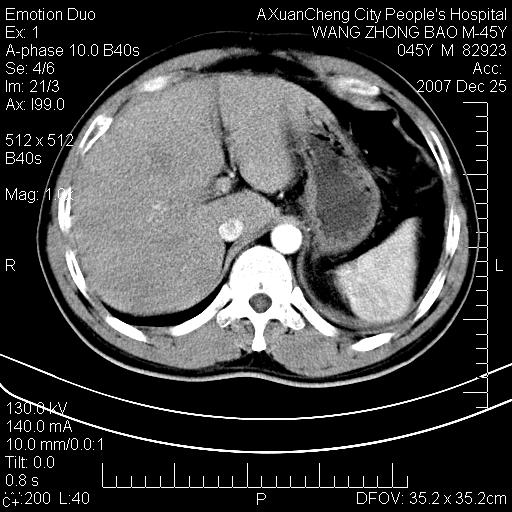

以下是引用qiuleiyu在2007-12-25 18:14:00的发言:[br]胰腺增大,周边渗出改变,肾前筋膜明显增厚,示少量积液.胆囊壁毛糙,周边少许渗出,胆总管壁厚,异常强化,然扩张不明显.结合病程急短;考虑;胆管炎,胆囊炎,胆源性胰腺炎可能大,请结合实验室检查及随访.

以下是引用lisihao在2007-12-25 14:23:00的发言:[br]急性水肿型胰腺炎[br]依据:1、胰腺弥漫性肿大,边缘稍毛糙;[br] 2、双侧肾周筋膜增厚,尤以左侧为甚(重要征象)[br] 3、双侧后胸膜增厚(刺激性炎症);[br] 4、结合病史,查血尿淀粉酶应该可以确诊。